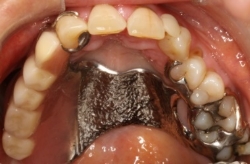

Bild 1 Markering på gipsmodell på den del av gommen och tänderna som planeras att tas bort under operationen. Tillhörande gom-/operationsplatta med klamrar (utan tänder i detta fall)

- Operationsplattan fästs med små benskruvar under operationen och en tamponad packas. Skruvarna och tamponaden tas bort ca 7 dagar efter operation. Plattan fungerar under denna tid som ett ”sårskydd” och för att du ska kunna komma igång att tala, äta och dricka.

- När benskruvarna tas bort måste operationsplattan justeras och anpassas till den uppkomna defekten/hålet. Detta görs genom en slags ”halvsulning” med ett mjukt silikonbaserat material.

- Operationsplattan får nu fungera som en temporär avtagbar tandprotes/obturatorprotes och fortsatta justeringar görs vartefter defekten/hålet läker och ändrar form.

- Framställning av den permanenta obturatorprotesen kan oftast påbörjas efter 6-12 månader efter avslutad kirurgi och eventuell strålbehandling. Efter denna tid har läkningen avslutats och defektens utseende anses vara stabil. Individuell skillnad föreligger.

- Den permanenta obturatorprotesen fästs med klamrar till dina egna kvarvarande tänder och ibland också till titanimplantat som får installeras.

Bild 2 A. Operationsdefekt efter tumörresektion B. Permanent obturatorprotes med gomplatta i metall och klamrar C. Protesen på plats i munnen.

A B C

Bild 3 Stor defekt större obturatorprotes

Bild 4 Mindre defekt mindre obturatorprotes